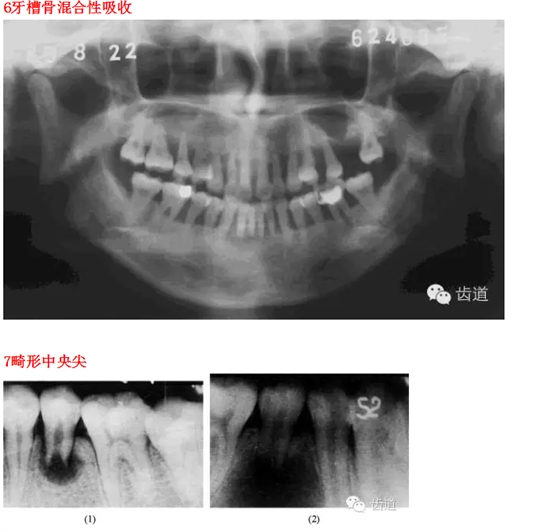

26種口腔病變X光片